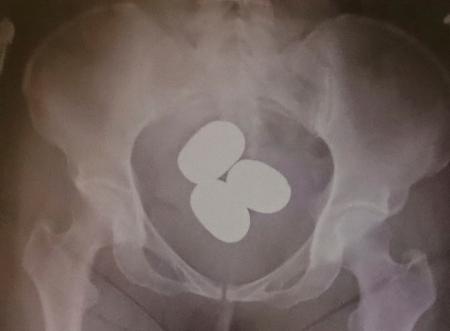

東京税関成田税関支署は24日、粉状の金を避妊具などに入れて体内に隠し、香港から成田空港へ密輸するケースが急増していると明らかにした。今年1~3月に押収しただけで時価総額は約12億円に上る。不安定な国際情勢を背景に金の価格は高騰しており、正規の輸入で納めなければならない消費税を免れ、利ざやを得る目的とみている。